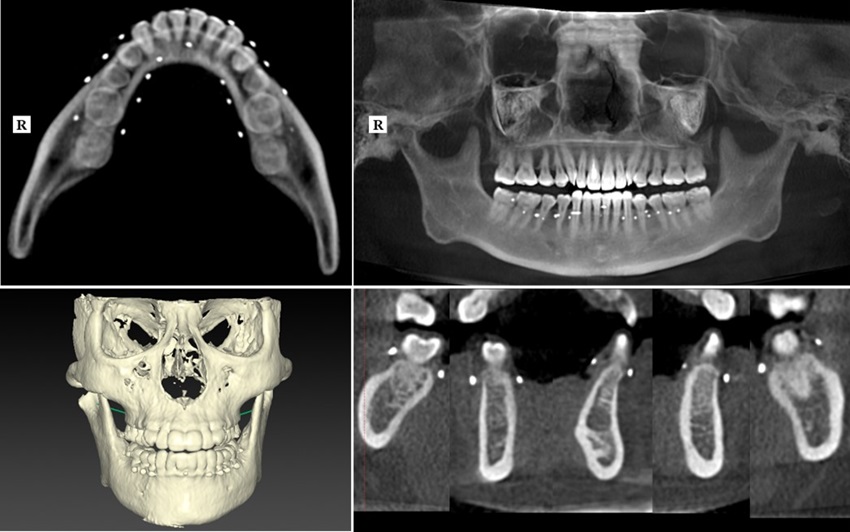

今回、ヒトに対する効果を検証するために、30~60代の中部大学女性職員48人を対象に、マルトビオン酸カルシウムを含む、または含まないタブレット菓子を摂取する2つのグループに分けて、24週間継続摂取するヒト臨床試験を実施しました。試験では、歯科用X線CT装置を用いた、顔面(上顎と下顎)の骨密度を、試験前後にそれぞれ測定を行いました(図4)。